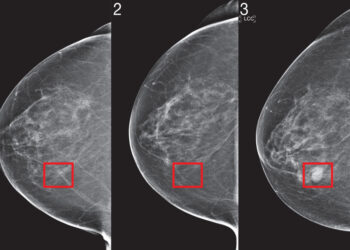

Për ta kapur kancerin më herët, duhet të parashikojmë se kush do e ketë atë në të ardhmen. Natyra komplekse ...